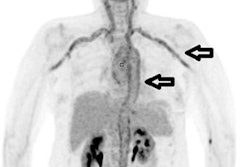

F-18 FDG PET/CT could be an effective tool for evaluating unexplained fevers -- and thus improving how quickly patients can be diagnosed, according to a study published online August 23 in Clinical Infectious Diseases.

The study results also suggest that using PET/CT for patients with "fever of unknown origin" could make care delivery more precise, wrote a team led by Dr. William Wright of Johns Hopkins University in Baltimore.